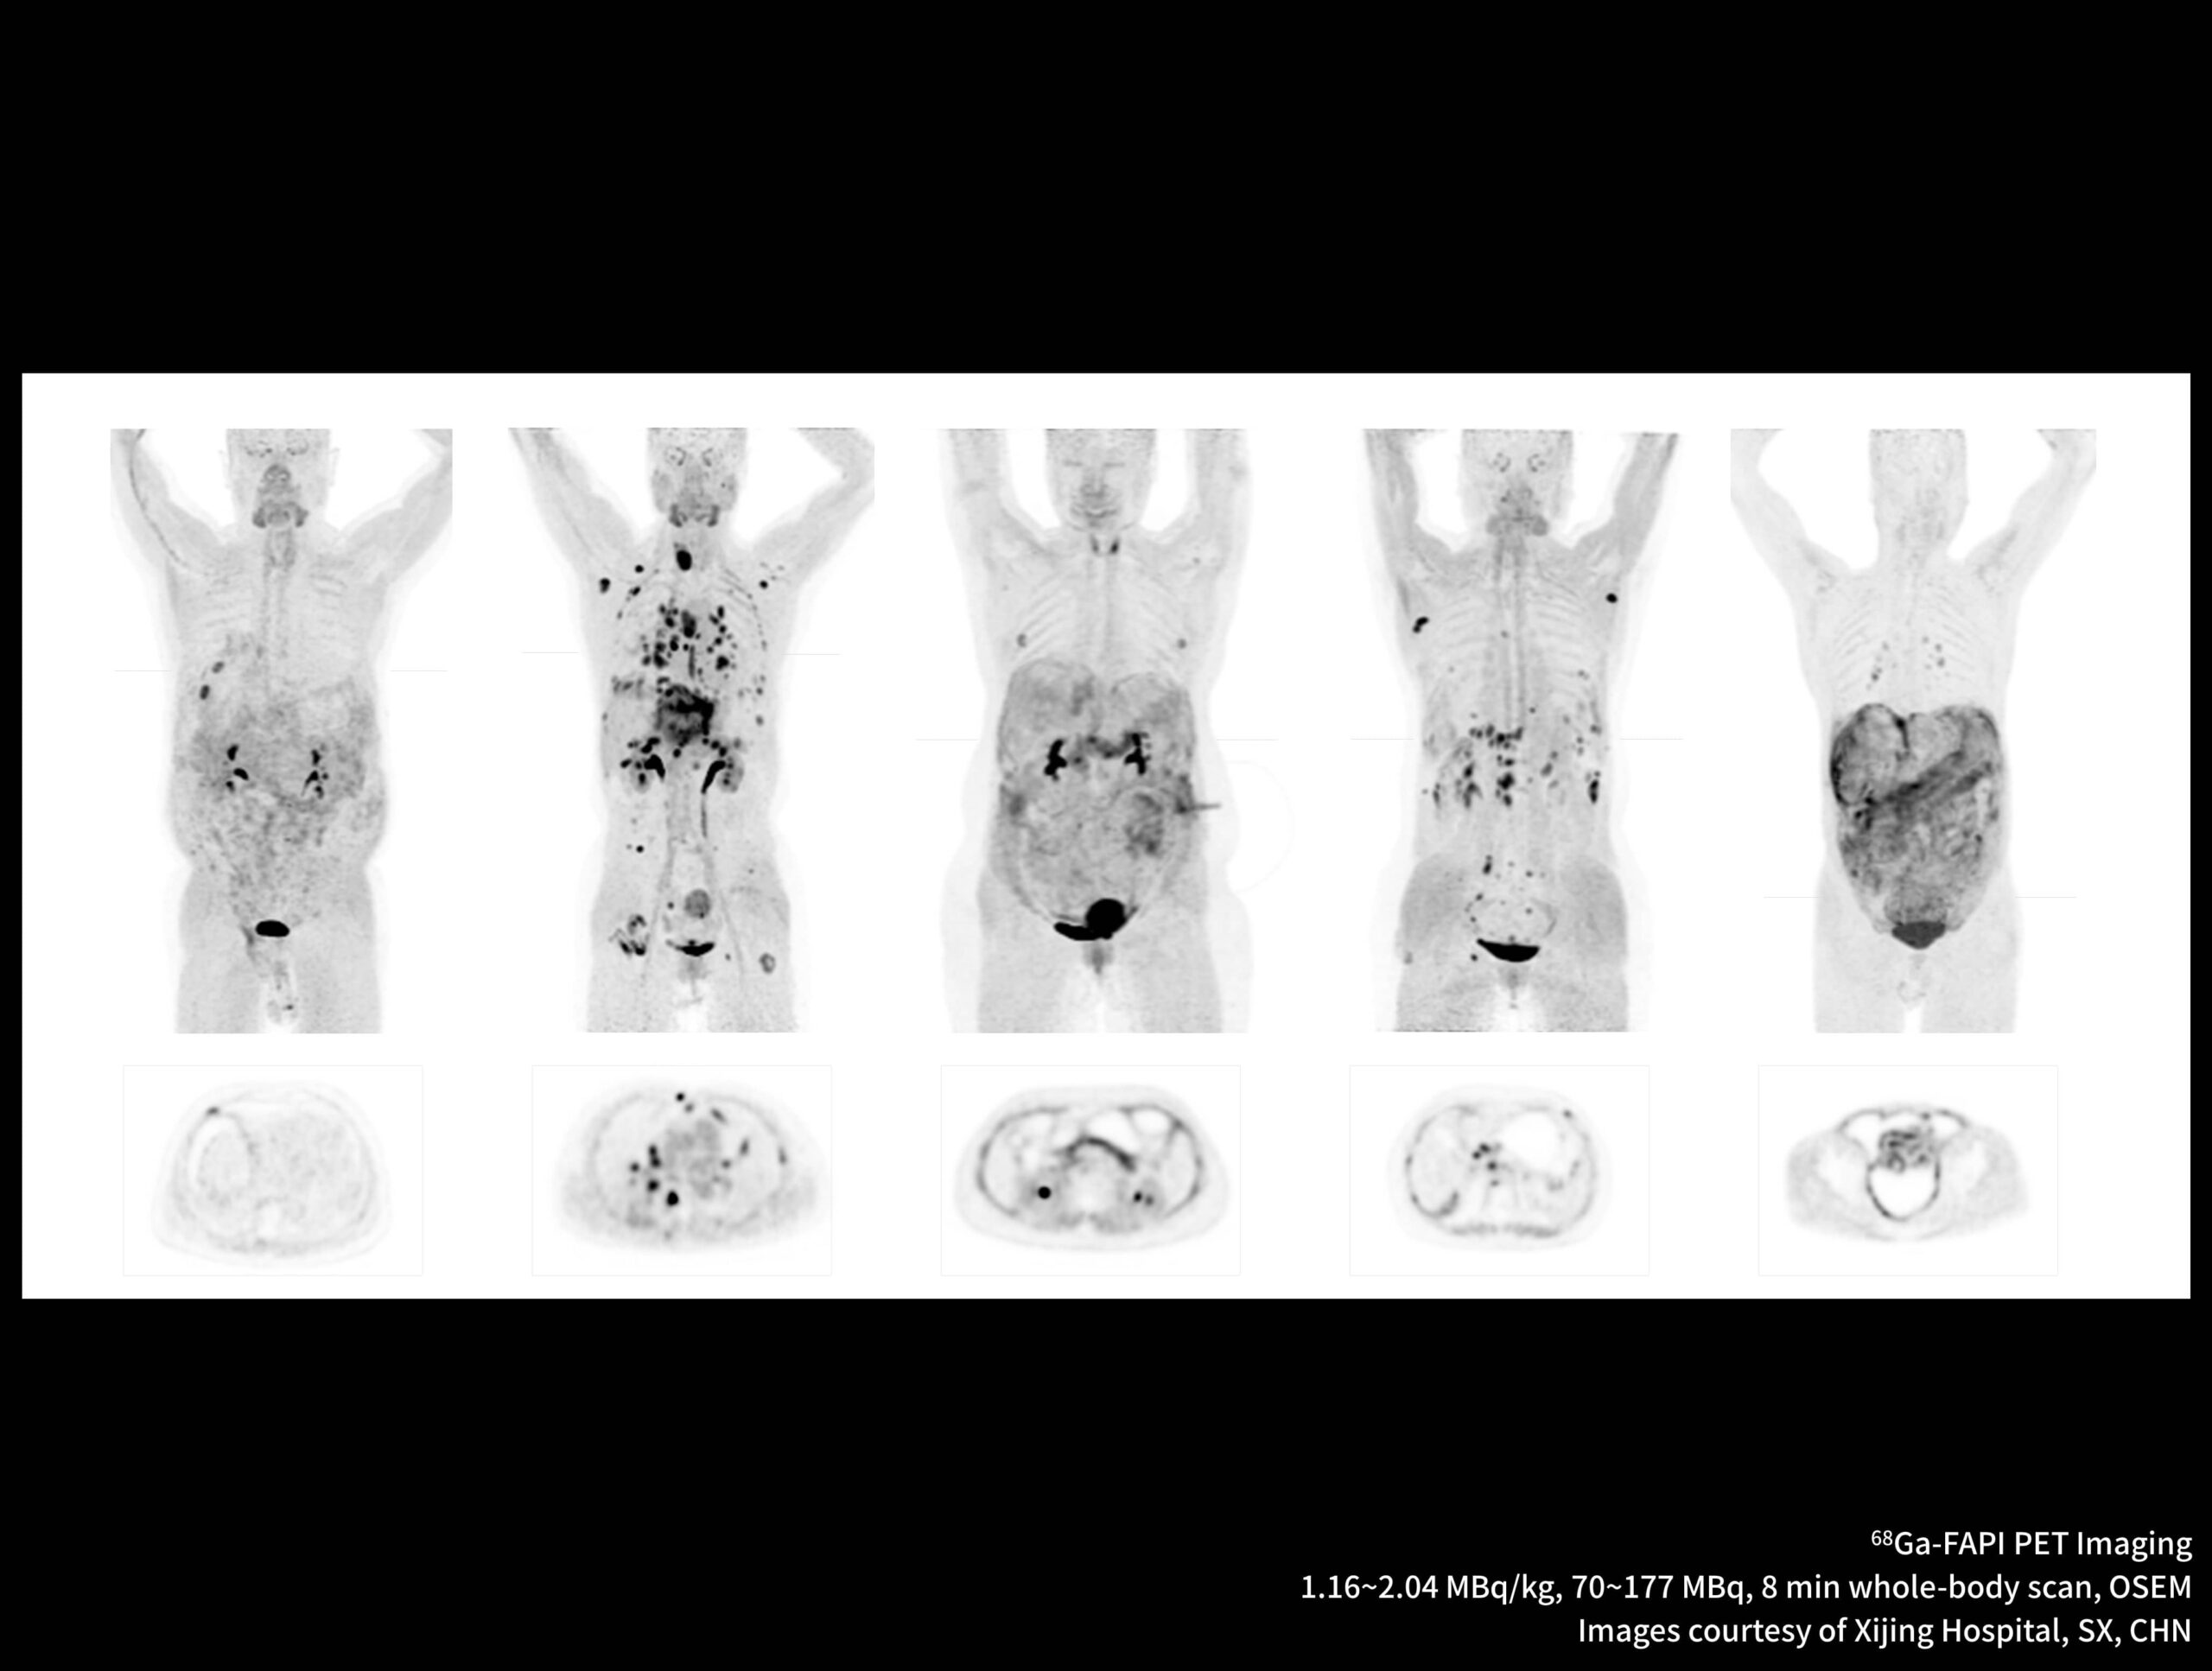

Imagistică PET/CT cu noi radiotrasori

Galerie de cazuri uMI Panorama

Imagistică de înaltă rezoluție obținută cu radiotrasor marcat cu galiu la doză redusă